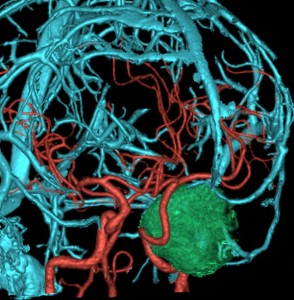

7歳の時に偶然発見された左海綿静脈洞外壁の類皮のう胞 dermoid cystで,多数の脳神経と皮膜が癒着するものです。この腫瘍は先天性の腫瘍なのでおそらく生まれた時からあったものです。10歳の時に手術摘出しました。画像は22歳の時の手術前のものです。何故2回も部分摘出したのかは,この類皮のう胞というのは脳組織や髄膜や脳神経にベトベト癒着してくっつく性質があるからです。海綿静脈洞内にある脳神経と剥離できませんでした。でも初回手術から12年無症状でしたし,2回目の手術後も無症状です。

左側の画像はガドリニウム増強のT1強調MRIです。壁が厚いと造影剤で増強されることがありますが,この壁はとて硬いです。